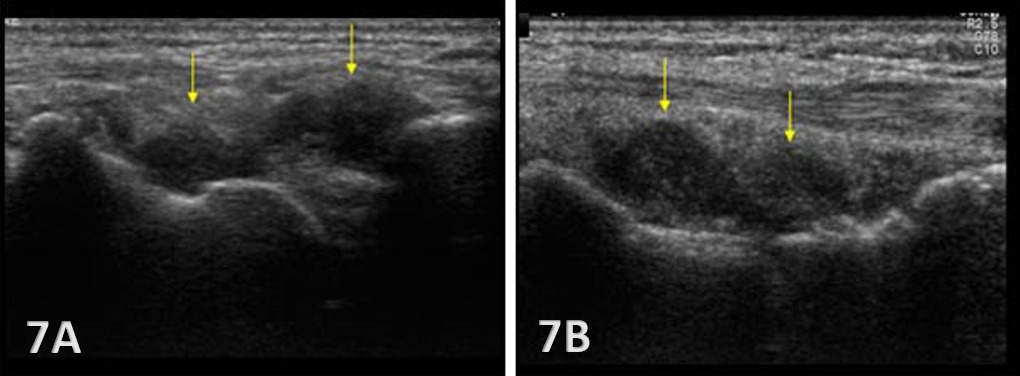

Anechoic or hypoechoic joint effusion and/or synovitis (synovial hypertrophy) and cysts within the joint.

Joint effusion is somewhat compressible and mobile when transducer pressure is applied to the area. This is different from synovitis, which appears as hypoechoic or isoechoic, non-compressible tissue within the joint recess. Synovitis may be associated with conditions such as rheumatoid arthritis, psoriatic arthritis, or other inflammatory arthropathies. Lastly, a ganglion cyst may appear as a well-defined, round or lobulated cystic structure with anechoic or hypoechoic internal contents. The cyst will usually have a small, smooth wall and exhibit posterior acoustic enhancement. These cysts will typically be minimally or non-compressible and painful.

Early Detection of Injury / Accurate Injury Grading: MSKUS can detect small anechoic or hypoechoic fluid collections in the radiocarpal recess that may be invisible to the naked eye. Finding this early will help guide treatment planning. Additionally, small ligament sprains or partial tears may be seen on ultrasound as irregular loss of normal fibrillar patterns.

Dynamic Functional Testing: Rehabilitation professionals can use MSKUS to dynamically stress the tissues with gentle wrist motion to reveal instability or soft tissue impingement between bones or abnormal findings such as cysts.